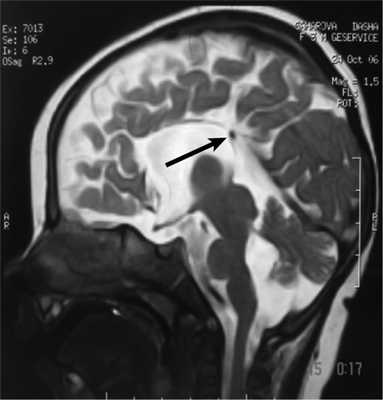

Рис. 3. МРТ головного мозга (сагиттальная проекция) больной С., 7 лет. АМТ (стрелка).